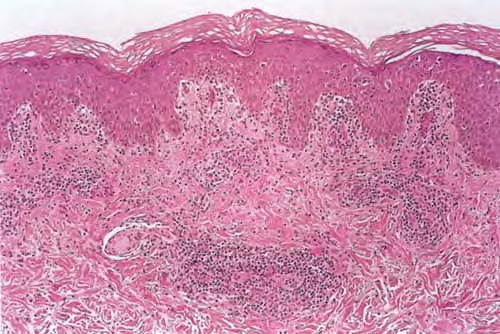

Atlas of skin histopathology

Mucha-Habermann disease = داء موشاهابرمان